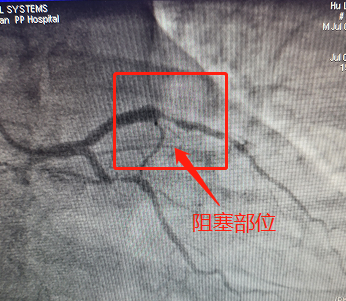

14:54分,患者被直接送到我院導(dǎo)管室行CAG+PCI術(shù),如術(shù)前所料,患者的左前降支中段完全閉塞。

術(shù)前